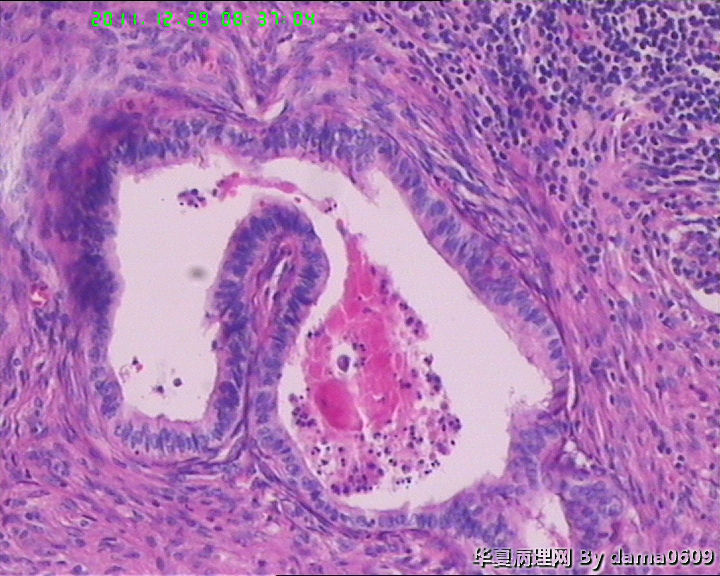

另一为小块囊壁样组织。镜下见卵巢间质内大量淋巴细胞、嗜酸性粒细胞浸润,间质出血。囊壁囊腔一侧见组织细胞、嗜中性粒细胞浸润,小血管增生(图1-9)。局灶见较多的平滑肌组织,内见有异位的子宫内膜组织(图10、11、12)。另于平滑肌组织间见到散在的小腺体(图13~30)。学生不解:1、老年人卵巢内可以出现平滑肌组织,如卵巢门处。此例如此多的平滑肌是正常的吗?   2、平滑肌间的小腺体若是异位的子宫内膜腺体但周围不见内膜间质成分。若非内膜异位腺体,学生又不知如何解释,尤其图19、20、21。请老师们指点迷津。感谢!!

• 感谢老师们一年来的支持,年终岁尾最后一贴,请老师们指教!!图13

图13